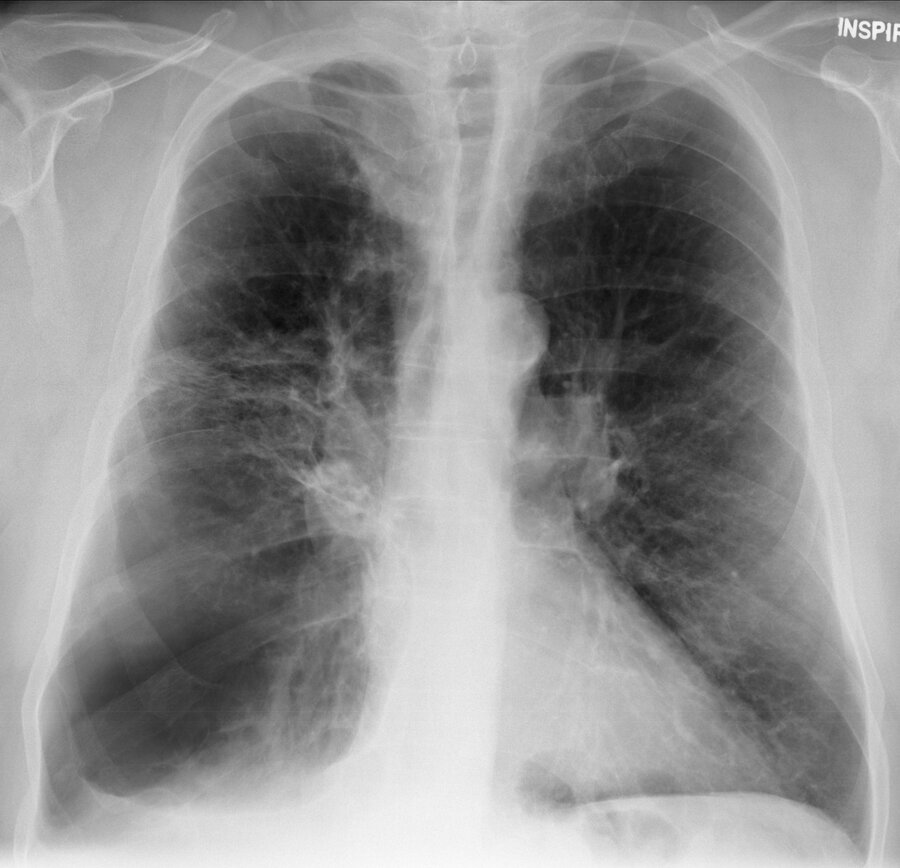

A 69-year-old man is evaluated for chronic dyspnea without cough. Pulmonary function demonstrates an obstructive defect that persists following bronchodilator administration.

Chest radiographs are shown.

Which of the following conditions is the most likely radiographic diagnosis?

Bronchiectasis

Bullous lung disease

Left lower lobe pneumonia

.Hodgkin lymphoma